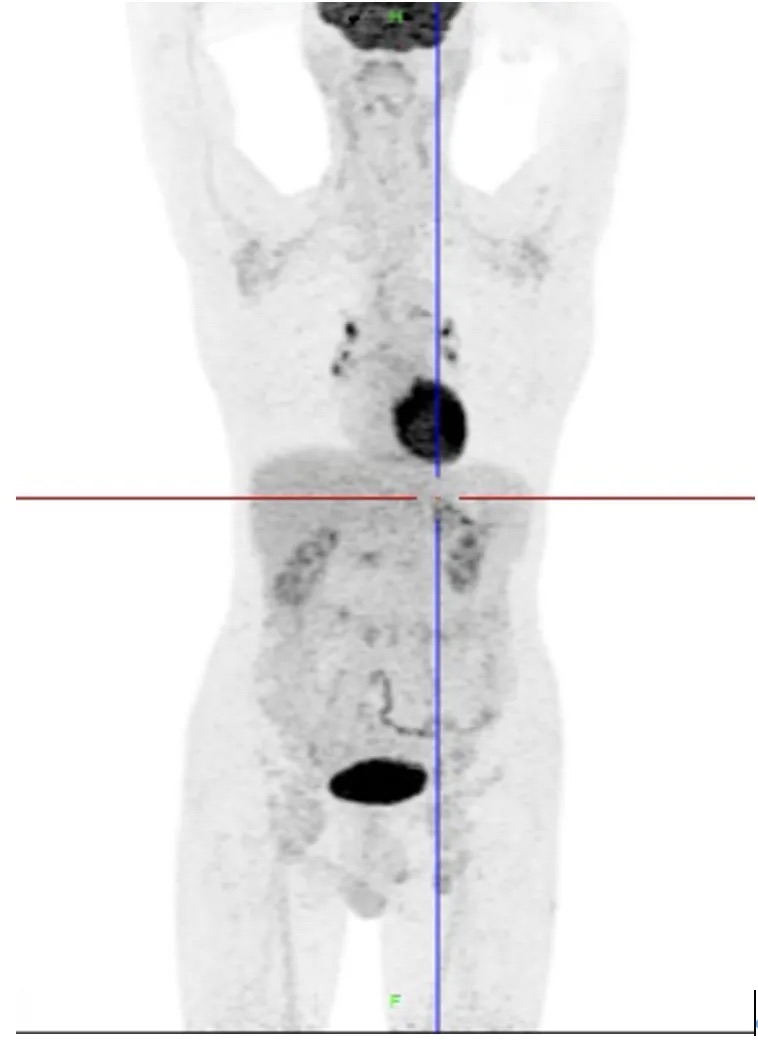

PET-CT检查

:1.双侧颈部、双侧锁骨上、双侧腋窝、腹膜后、双侧髂血管旁、双侧腹股沟多发肿大淋巴结,氟代脱氧葡萄糖

(FDG)代谢增高,淋巴瘤考虑;2.纵隔及双肺门多发淋巴结,密度偏高,炎性增生倾向,建议复查。(图1)

图1 患者基线时的PET-CT检查